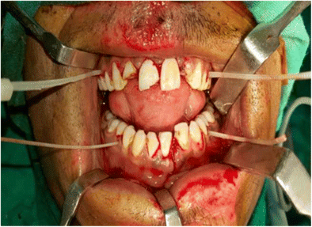

Fig. 1

Fig. 2

Fig. 3